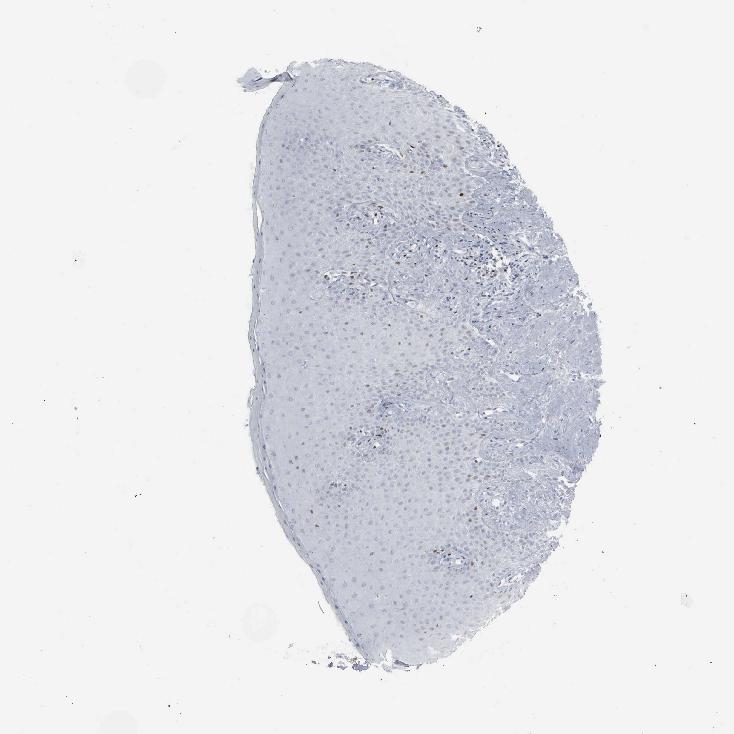

TISSUE PRIMARY DATA ORAL MUCOSA Show tissue menu

ORAL MUCOSA - Antibody stainingi

Antibody staining in the annotated cell types in the current human tissue is reported as not detected, low, medium, or high, based on conventional immunohistochemistry profiling in selected tissues. This score is based on the combination of the staining intensity and fraction of stained cells.

Each image is clickable and will lead to virtual microscopy that enables deeper exploration of all samples and also displays staining intensity scores, fraction scores and subcellular localization as well as patient and tissue information for each sample.

Antibody CAB000116

Squamous epithelial cells Not detected